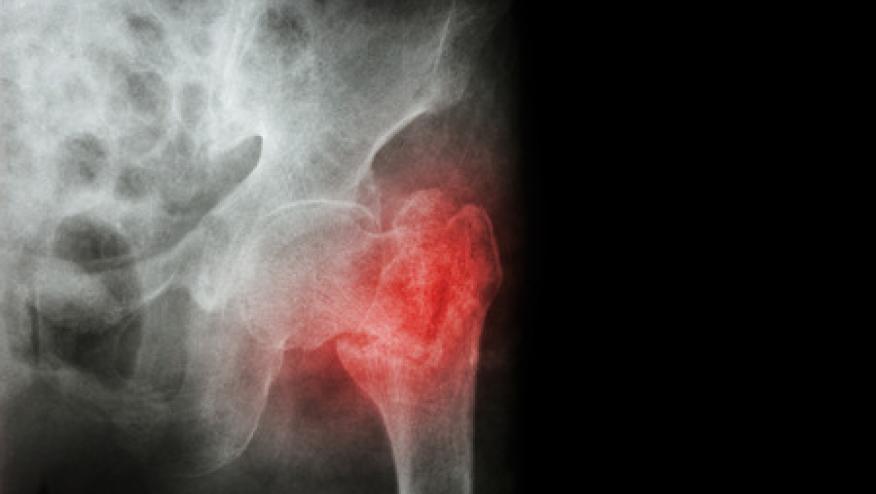

Finally, under-prescribing of bone-strengthening medications among patients at high risk of fracture has become a "Crisis in Osteoporosis Care," according to the ASBMR. "Most recently, fewer than 20% of hip fracture patients are started on osteoporosis treatments after their fracture. Ten years ago that number was 40%," said Honig. "The goal has been to start 80% to 90% of hip fracture patients on bone-strengthening treatments," he added.

This decrease in use of osteoporosis medications has been linked to fears about atypical fractures of the femur among long-term bisphosphonate users, he explained. In one study presented at the ACR meeting, researchers from Dartmouth Hitchcock Medical Center in Lebanon, N.H., searched the literature for reports of this, and found that the incidence of subtrochanteric or diaphyseal fractures ranged from 0.02/1,000 patient-years of treatment to 3.4/1,000.